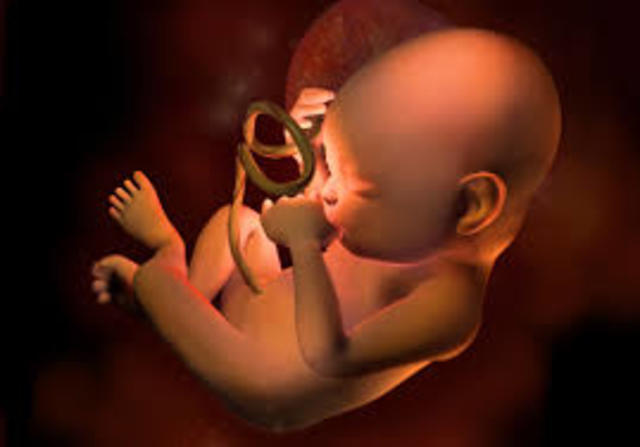

Semana Ocho

Ya tiene párpados,labio superior, nariz y orejas se están empezando a formar. El cuerpo se está alargando, pueden reconocerse lo que serán brazos y piernas, y es posible ver el esqueleto a través de su piel, que es translúcida.El esqueleto está formado por un cartílago suave todavía, no son huesos.

Hasta ahora, el embrión dependía del saco vitelino que, según se cree, le proporciona nutrientes.Entonces cuando la placenta asume la función de alimentarlo a través del cordón umbilical